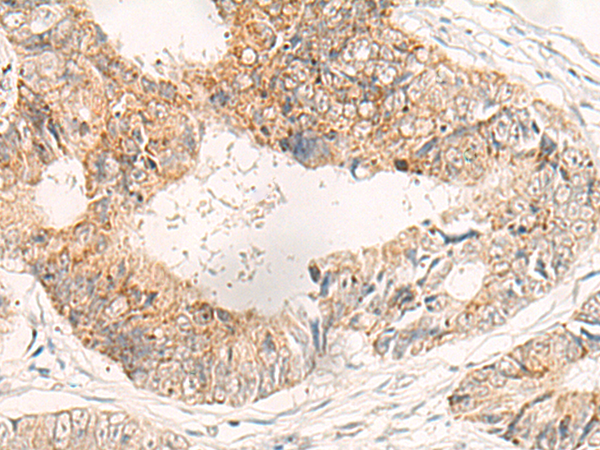

ELISA, IHC

IHC positive control:

Human tonsil and Human colorectal cancer

IHC Recommend dilution:

30-150